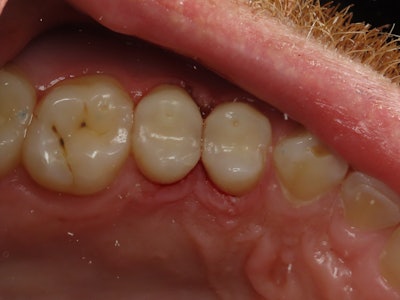

A patient presented for class II restorations due to primary decay on the interproximal surfaces of teeth #12 and #13 (Figure 1 and 2). Clinically the tooth was cold-tested and confirmed a normal response to cold stimulus.

Figure 2: Pre-operative intraoral photo.